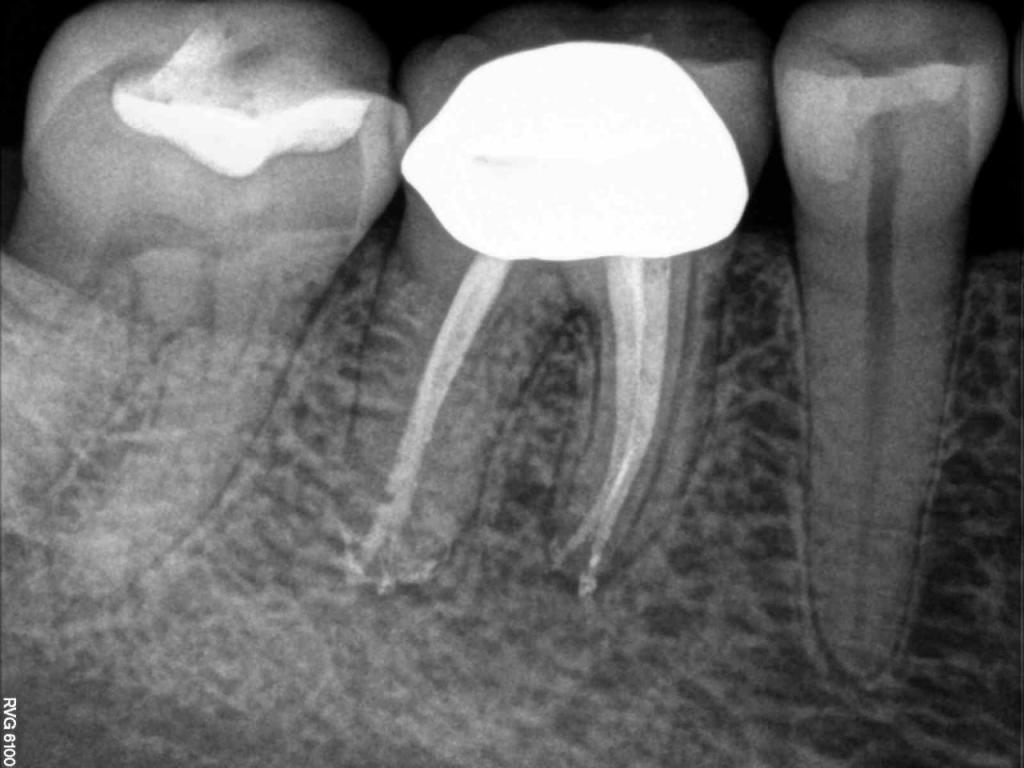

Although the primary use of visual documentation is for patient charts, dental images provide a meaningful way to communicate with patients about their care needs. Digital imagery is a vital tool for educating patients and an essential way to share information with office staff, colleagues and referring doctors. Digital technology has allowed Southcenter Endodontics to enhance our practice and improve the delivery of care to our patients. Below you will see images of “Before” and “After” scenarios. By clicking on a thumbnail image below, you will be able to see and a larger view of the x-ray taken at Southcenter Endodontics and notations made regarding each film.